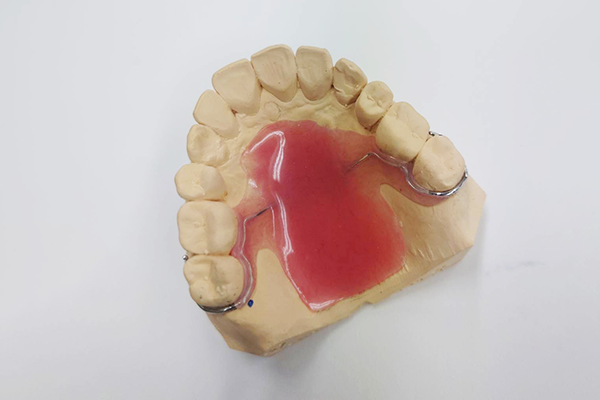

SLP(サブリンガルプレート)※下顎用

SLP(サブリンガルプレート)とは、日本歯科大学名誉教授の丸茂義二先生が考案された、歯ぎしりや食いしばり・睡眠時無呼吸症候群などを効果的にコントロールするための装置です。下顎の内側に装着する、小さな入れ歯に似た形で、低位舌になっている舌を前方に押し出すことができます。このことによって、歯ぎしり・食いしばりの軽減が期待できます。小さくできていますので入れ歯のような異物感なく使用できます。SLPは舌の下に入れて使用するタイプの装置ですので、睡眠時だけではなく、日中も装着したままで過ごすことができます。